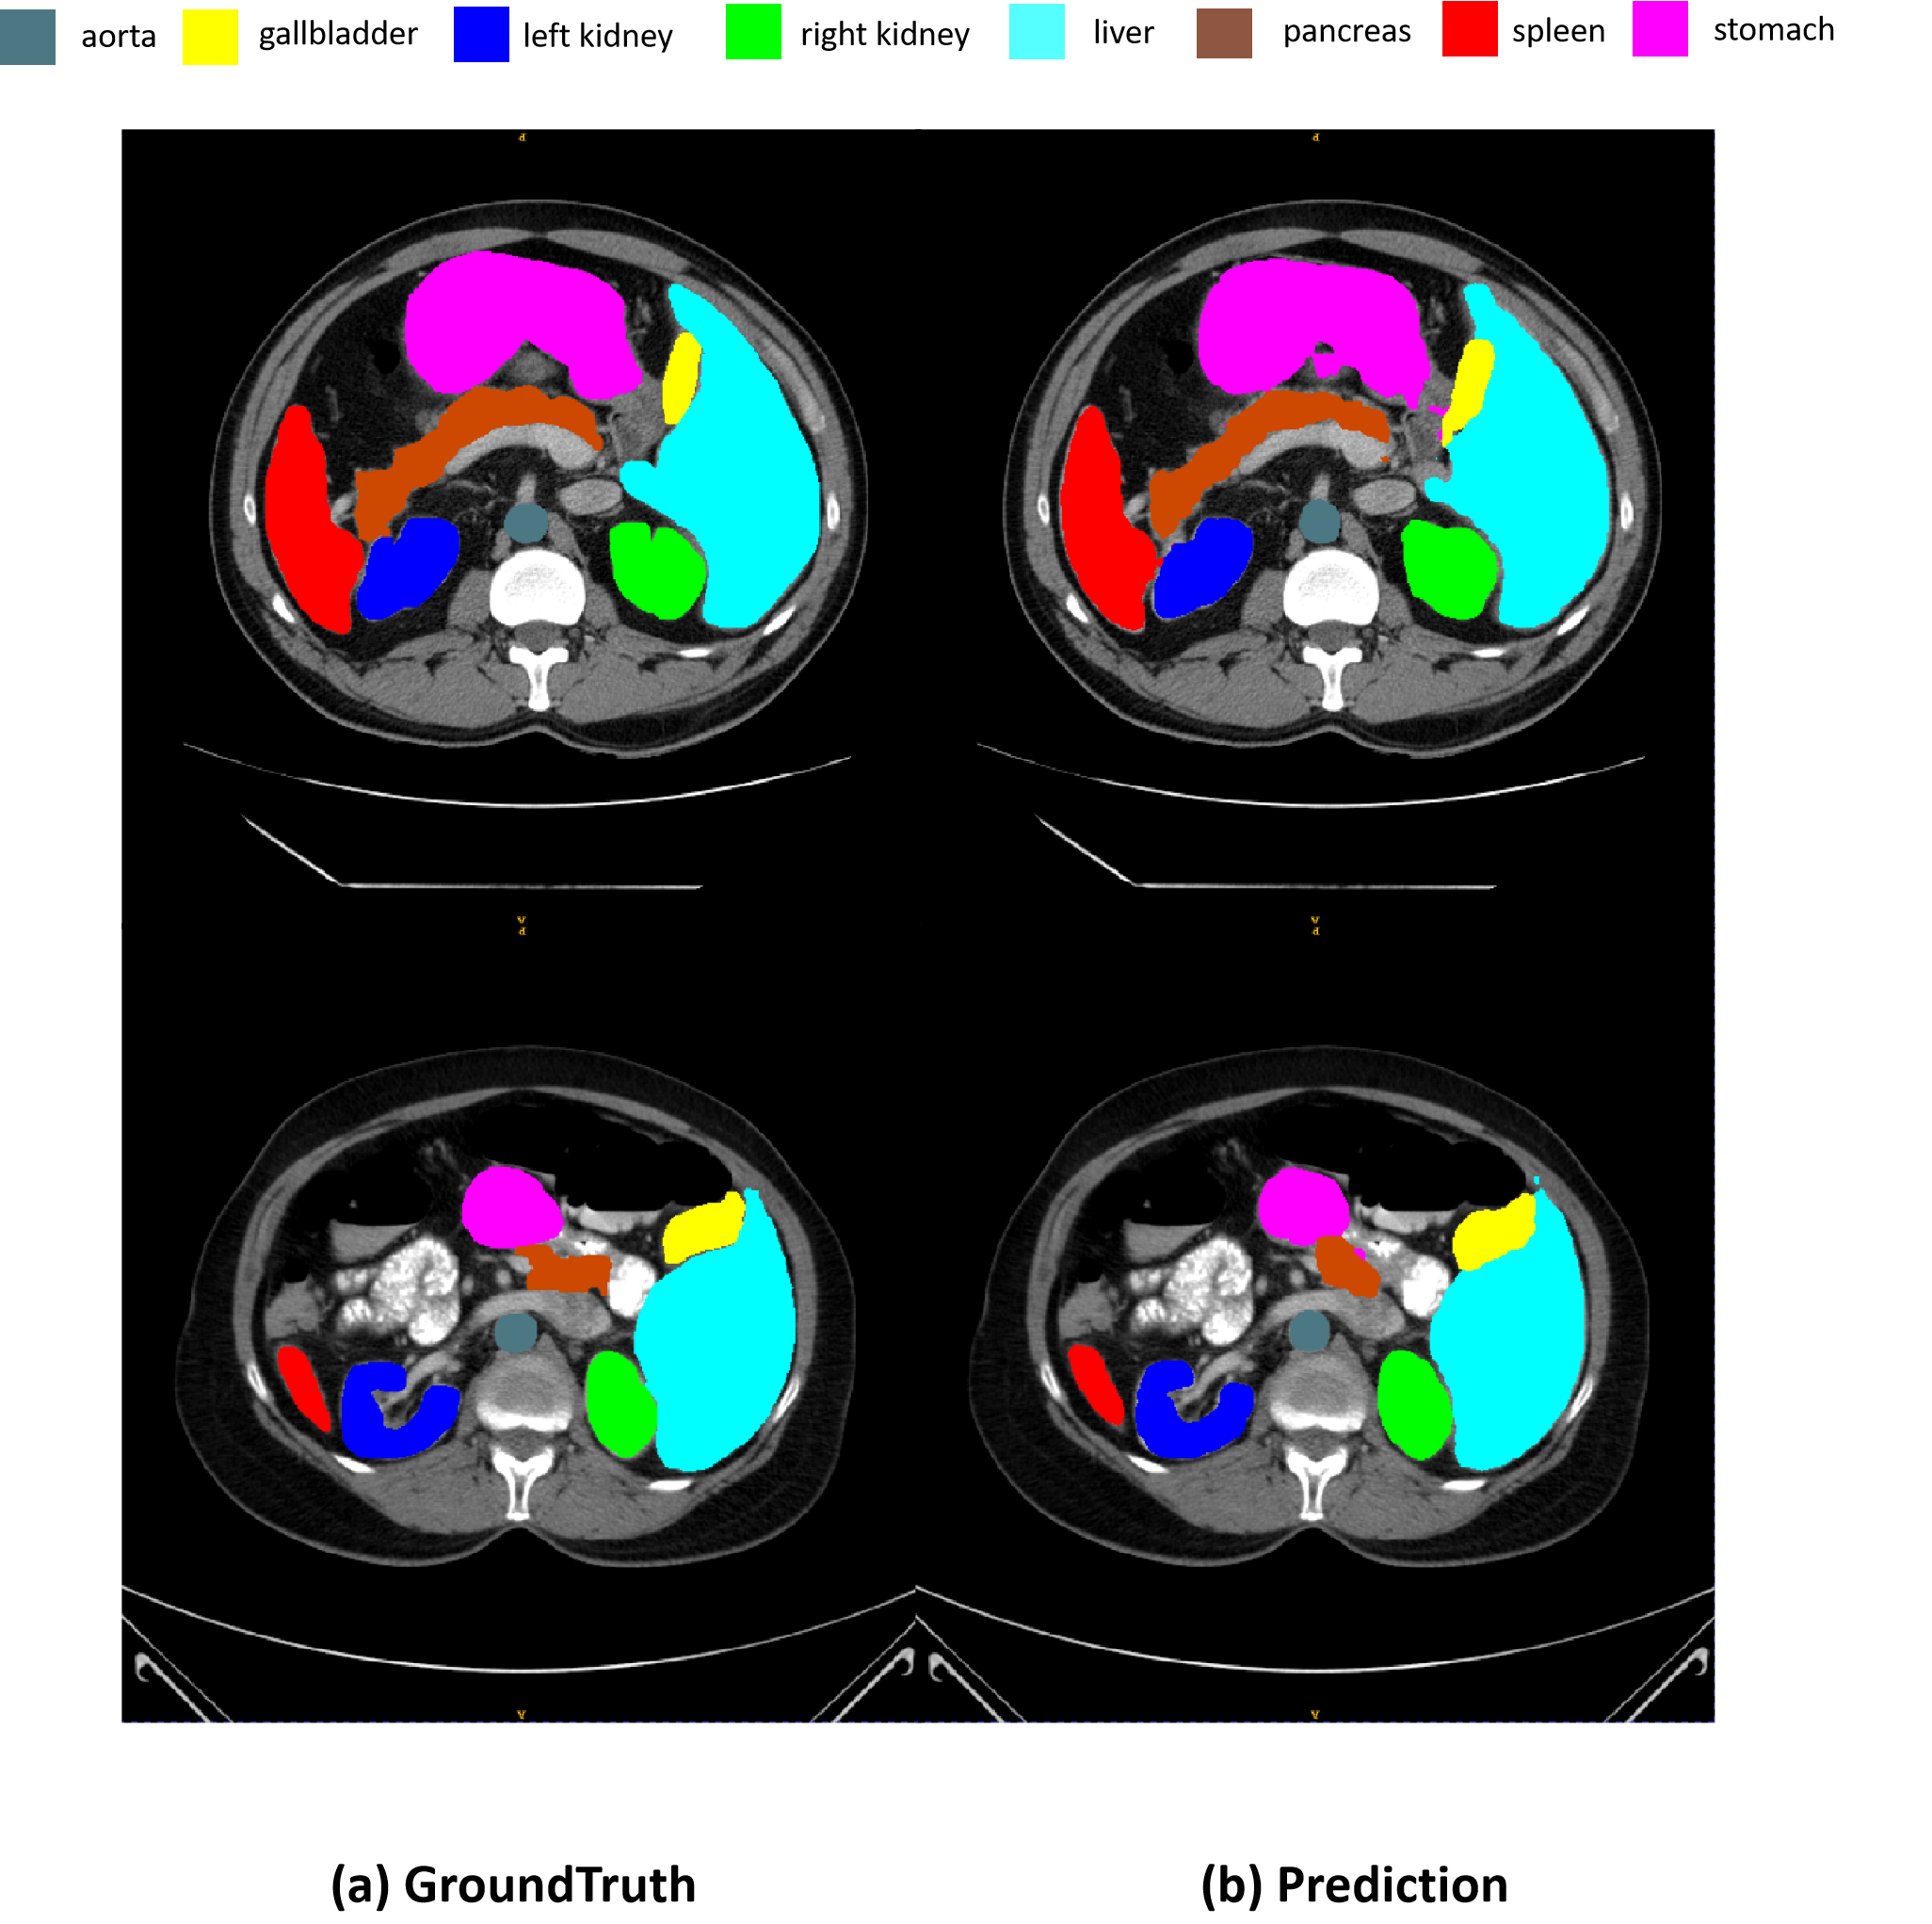

Table.I reports experiment results and comparison with other state-of-the-arts methods. Our proposed method achieves 79.45% DSC and 35.35mm HD95 scores. We also observe that the value of learnable weight parameter is 0.44. Our method achieves a competitive score while surpassing most of state-of-the-art methods. Some segmentation results are shown in Figure.3. However, the design of integrated CNN Encoder and learnable weight parameter can be modified to analyze and evaluate the performance of the proposed approach. We believe that utilizing a Transformer or other effective network design will yield even higher performance. In the future, we will explore advanced design choices to achieve the best results.

Refer to caption

Figure 3: Segmentation results on Synapse dataset.